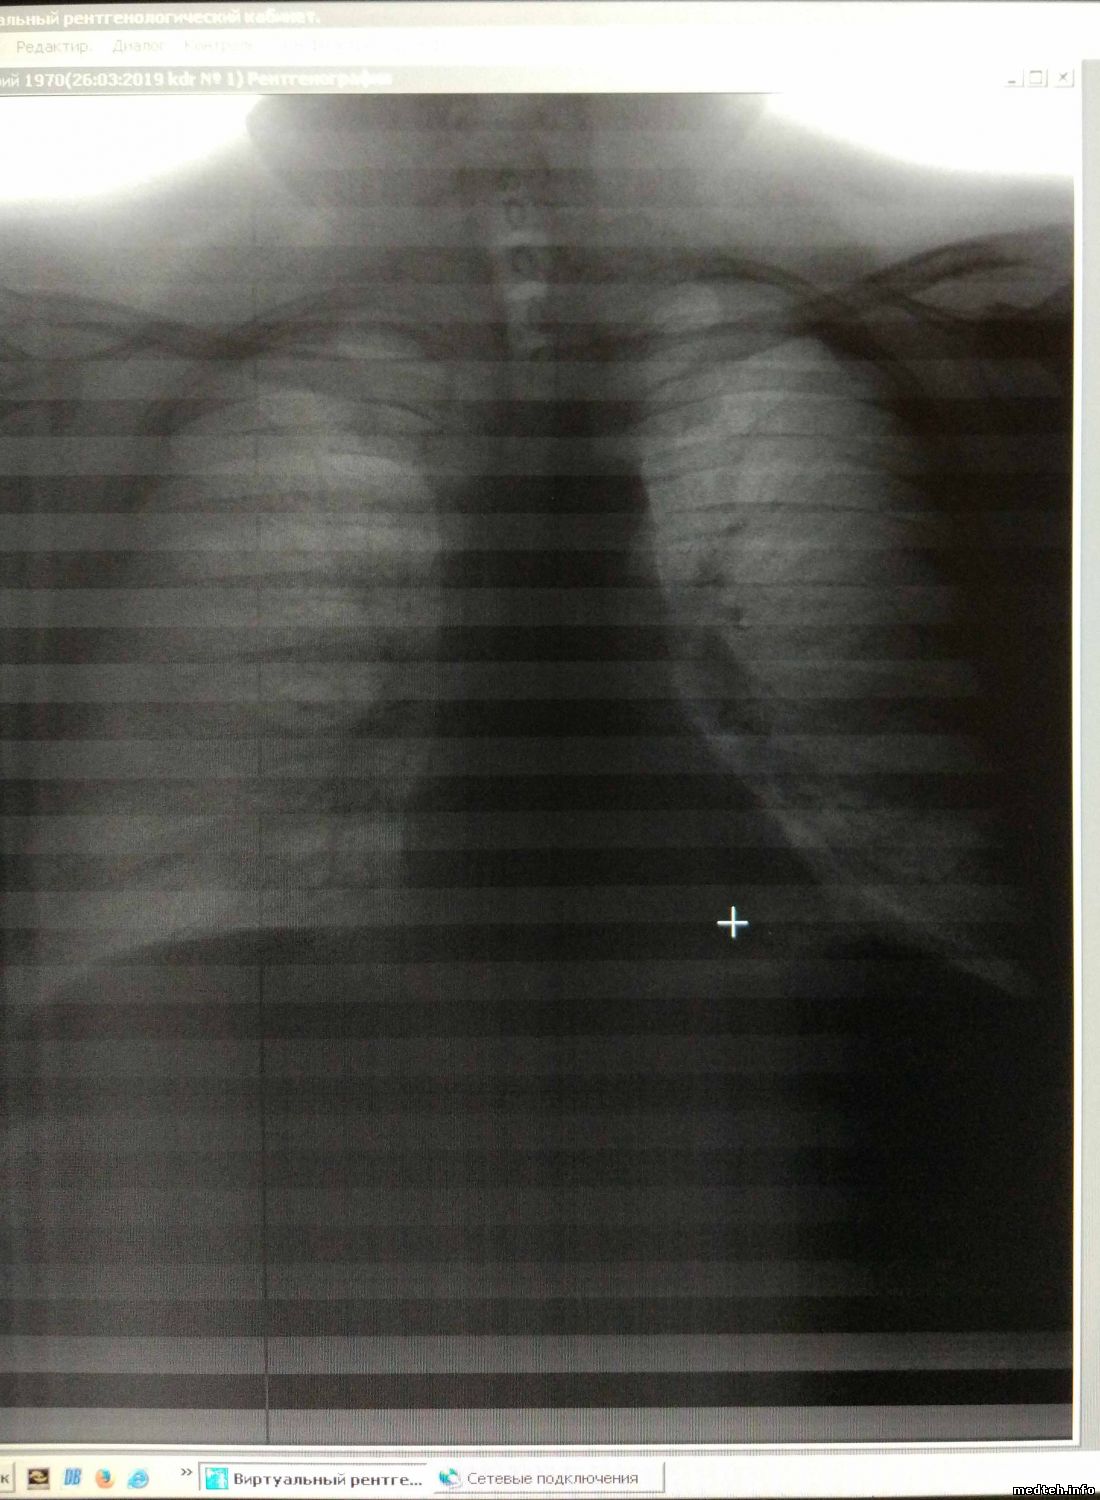

Есть в хозяйстве такой "Взгляд орла", в целом за прошлые года проблем с ним было не много, а вот сейчас не могу понять - периодически полосит картинка, куда мог, залез, поменял часть кабелей (грешил на наводки), детектор проверить негде. Главное, нестабильная неисправность - то есть, то нет..

Может кто-нибудь посоветовать, в какую сторону копать ? Фотки прилагаю..

Судя по фото-виноват детектор,но как вариант-плата обрботки видеосигнала в компе лаборанта,к ней подходит кабель от детектора.

По моему скромному опыту - на сканирующих флг - подобная "тельняшка" легко корректируется регламентной процедурой калибровки.